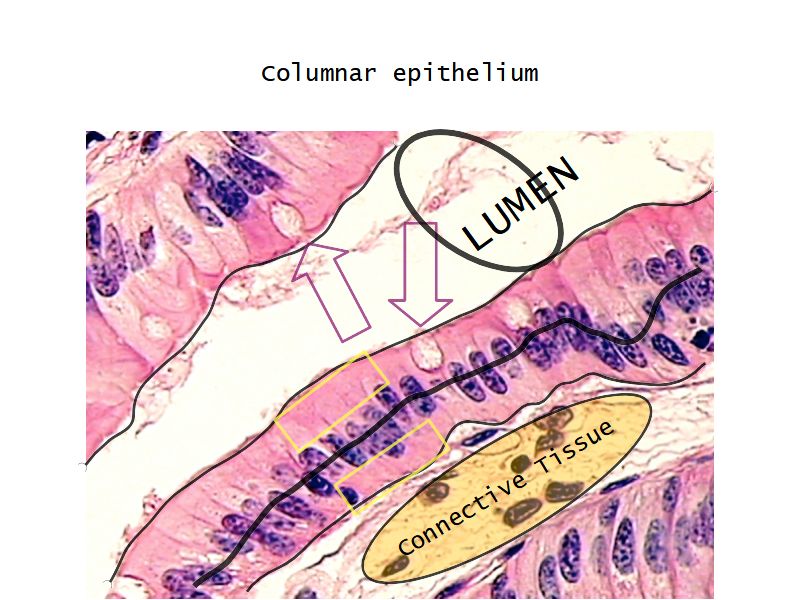

Respiratory epithelium

- Columnar